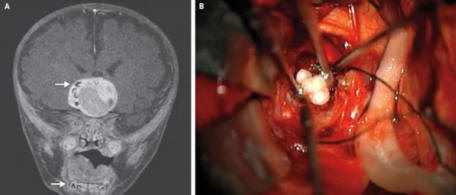

4. Izkazalo se je, da je redek tumor v otrokovih možganih zob

Fotografija iz odprtih virov

Maryland 4-mesečni dojenček je morda prvi oseba, ki je imela v možganih tumor, ki se je izkazal za zob. Prvič zdravniki so sumili, da nekaj ni v redu, ko se je zdela otrokova glava začel rasti hitreje, kot je značilno za otroke njegove starosti.

Pregled možganov je razkril tumor, ki ga je vseboval strukture, ki zelo spominjajo na človeške zobe, običajno najdemo v spodnji čeljusti. Tumor je bil odstranjen in zdaj fant čuti sami dobro.